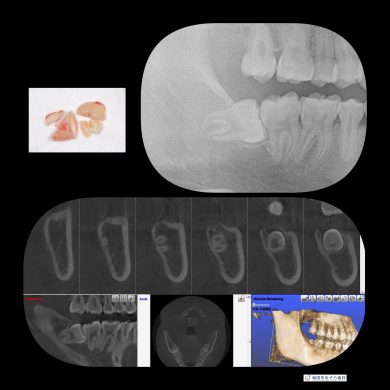

横向き親知らずの抜歯症例

院長はこのような横向きに埋まっている抜歯ケースも

1000症例以上の手術実績あり☆

横に埋まっている場合はCT撮影で安心です☆